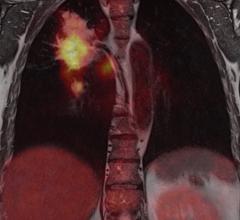

The last decade has seen a significant advancement in imaging technology due to developments in the hardware and software space. It was clear to the radiologists, clinicians and imaging scientists very early on that no single imaging modality, be it magnetic resonance imaging (MRI), computed tomography (CT) or positron emission tomography (PET) could meet all the needs of a clinician treating a patient.

The introduction of hybrid technology — positron emission tomography/computed tomography (PET/CT) and single-photon emission computed tomography (SPECT)/CT -— has revolutionized the imaging world. This technology allows the combination of the exquisite anatomic details provided, for example, by CT, with the important and much needed functional, physiologic or metabolic information provided by molecular imaging.

At RSNA 2012, Philips Nuclear Medicine is introducing new clinical innovations for its positron emission tomography/computed tomography (PET/CT) systems.